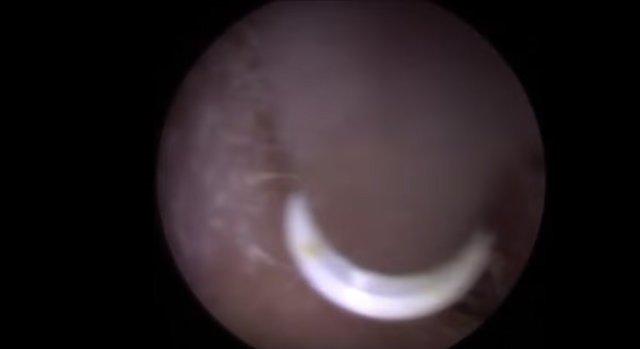

30 yıl boyunca geçmeyen bir baş ağrısı ile yaşayan bir kişi gittiği doktoru şoke etti. Yıllarca baş ağrısı çeken 59 yaşındaki adamın yaşadıkları kan dondurdu. Adamın kafasından öyle bir şey çıktı ki, doktorlar bile şaştı kaldı. İşte şoke eden olayın detayları...